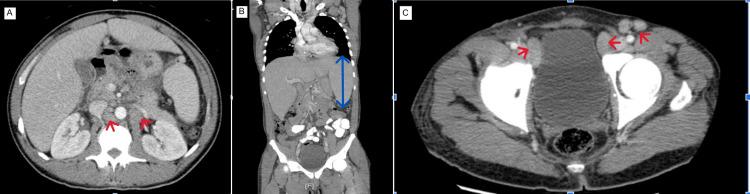

Angioimmunoblastic T-cell lymphoma (AITL) is a rare and aggressive form of peripheral T-cell lymphoma (PTCL). It can present with signs and symptoms that have broad differentials, including fevers, night sweats, and skin rashes. In this case report, we present an interesting case of a young male of Nigerian descent with recently treated malaria who presented with such symptoms and a picture that was complicated, due to an inconclusive excisional biopsy for lymphoma. He was later diagnosed with AITL. Given the patient's recent exposure to malaria, we will discuss the potential role malaria has in the development of AITL.

血管免疫母细胞性T细胞淋巴瘤(AITL)是外周T细胞淋巴瘤(PTCL)的一种罕见且侵袭性的类型。它可表现出具有广泛鉴别诊断的体征和症状,包括发热、盗汗和皮疹。在本病例报告中,我们呈现了一例有趣的病例,一名有尼日利亚血统的年轻男性,近期患疟疾并接受了治疗,他出现了上述症状,且由于淋巴瘤切除活检结果不明确,病情较为复杂。他后来被诊断为AITL。鉴于该患者近期感染过疟疾,我们将讨论疟疾在AITL发生发展中可能扮演的角色。